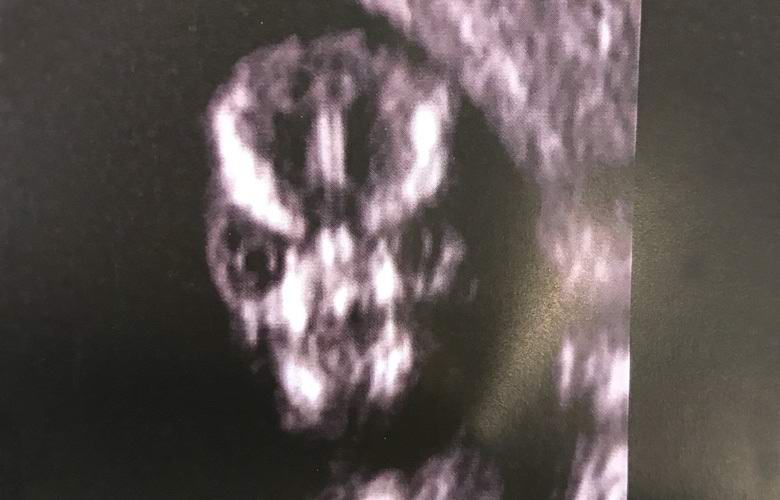

Terhes Sharney Turner a kórházba látogatott a magzat szonográfiáját, és egy heves arcot észlel az ultrahangos készülék képernyőjén, vagy egy hátborzongató szörnyre, vagy egy idegenre a bolygó.

Az ultrahang szakember úgy dönt, hogy arcát szkennel a fiam, és kiderült, hogy ez a legborázatosabb dolog amit valaha láttam az életemben. Valóban emberi néz ki a koponya ultrahang alatt? Érdekes, hogy mindig ilyen ijesztő vagy csak annyira szörnyű a baba?